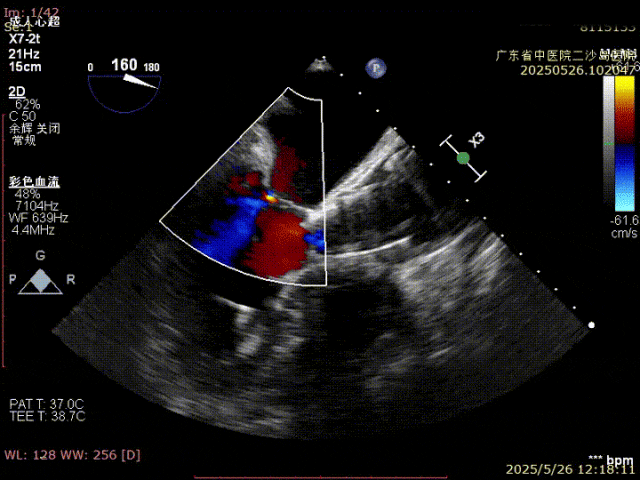

超声评估,深度符合DSA评估深度,约瓣下4mm左右,存在明显无冠窦侧压缩,准备进行瓣膜脱钩释放。

TauruMax脱钩释放阶段优势明显,脱钩过程稳定易控制,调弯后良好的同轴,脱钩后无位移,释放后,无冠窦侧仅1mm自同轴调整。

最终造影评估可见,瓣膜封堵良好无反流,无冠窦侧大约瓣下4mm位置,瓣膜形态良好,右窦中心位下,瓣膜显影点处于1:1:1状态,实现了良好的CA对齐。

超声评估也未见瓣周漏,深度良好,瓣架压缩充足,手术完美结束。

术后超声提示:人工瓣功能正常